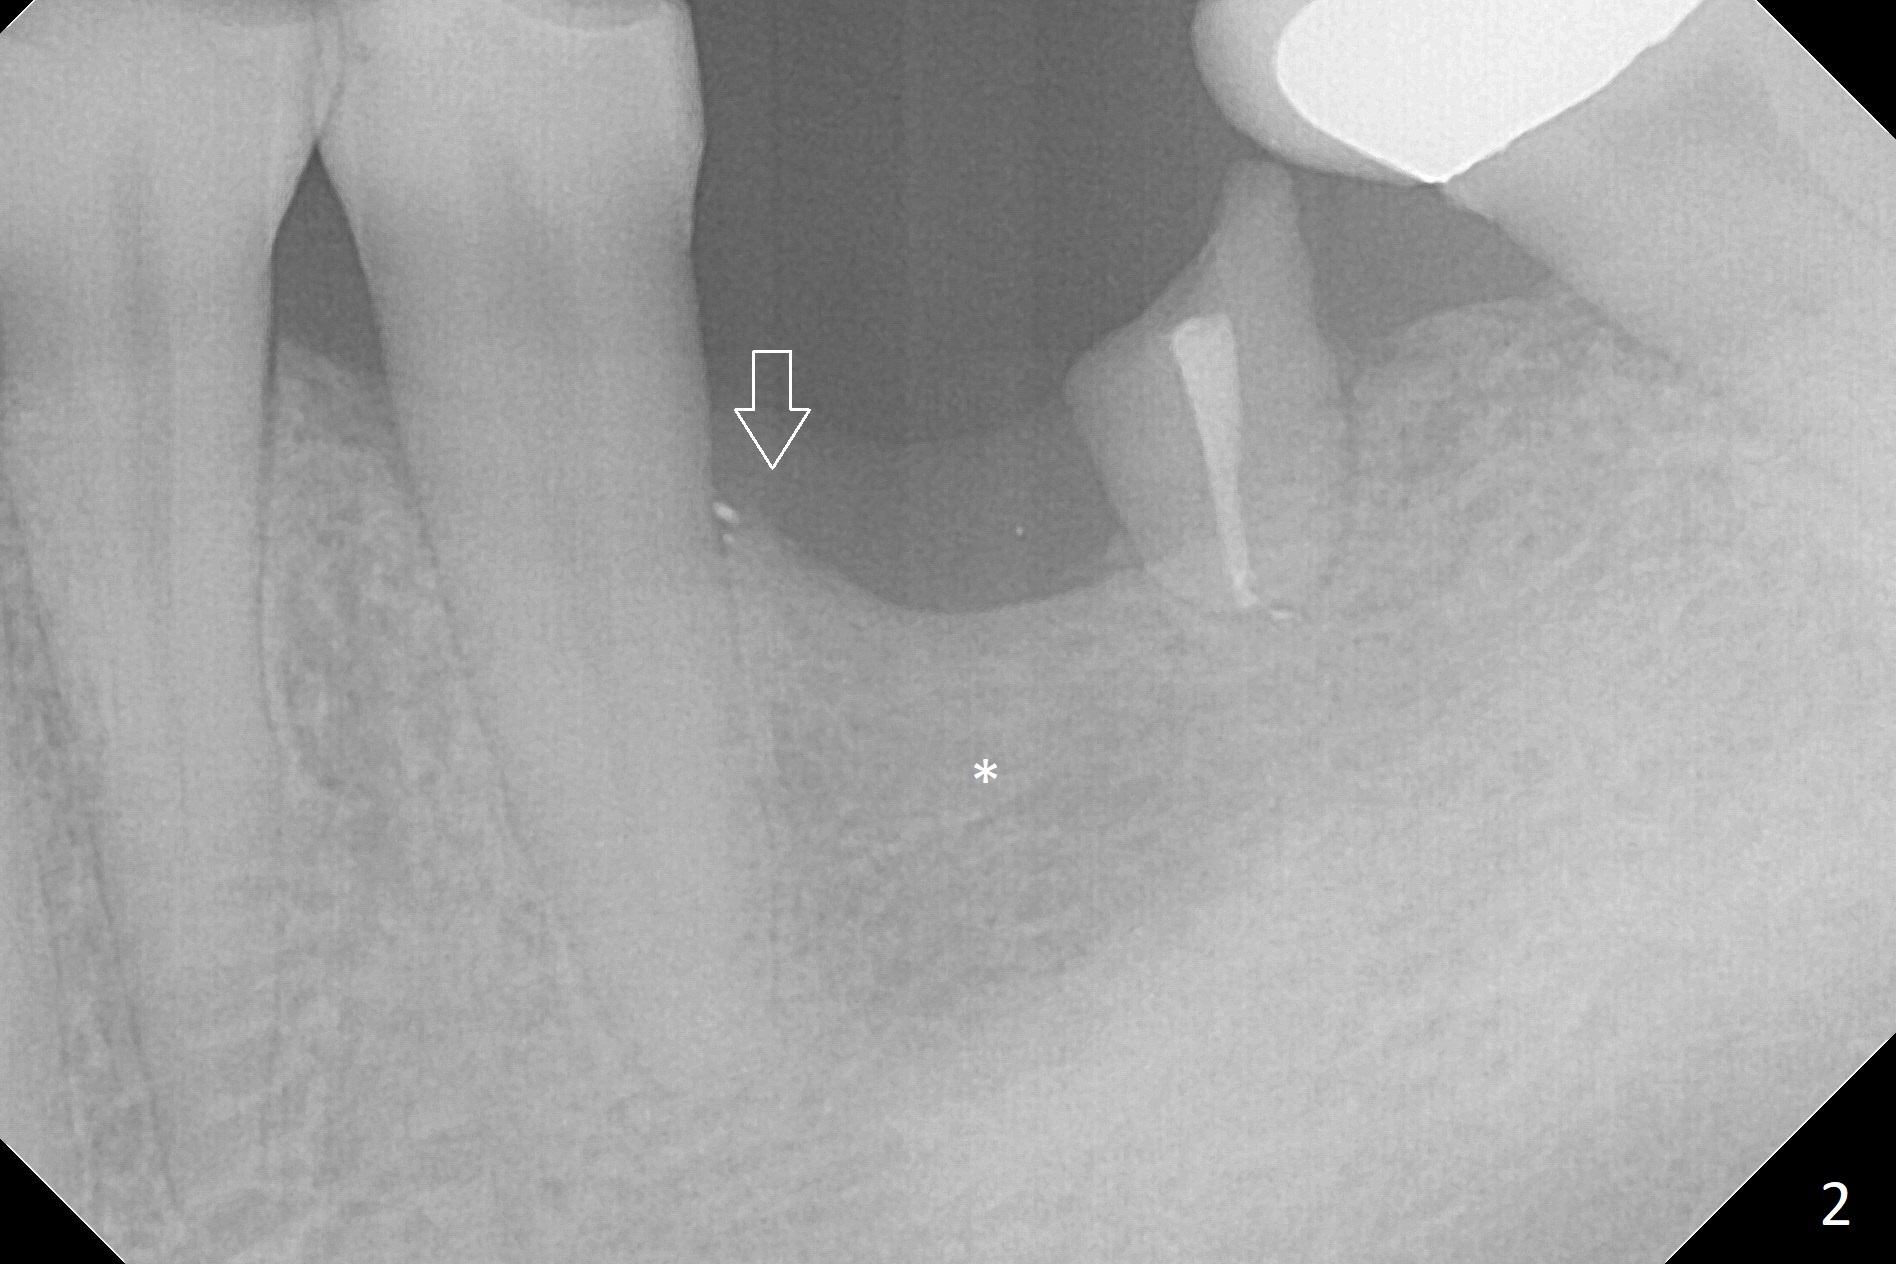

A 50-year-old man will return for #19 implant placement following the one at #30. In the last 9 years, the tooth have broken down with formation residual roots and loss of one of them (Fig.1,2). More important is the coronal portion of the alveolar bone becoming apparently thinner (Fig.2 *). There is also bone loss associated with the neighboring tooth (arrow). It is expected that the implant to be placed will be narrower and/or shorter than the one at #30. After removal of the distal residual root, use Magic Split as a scalpel to extend an incision mesially and start bone expansion, followed by Magic Expanders and IS drills if needed. Take preop photos to show the atrophic mesial ridge.